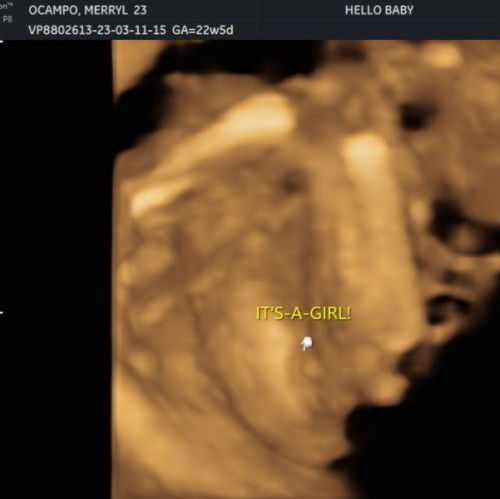

Team July (EDD July 10,2023 )

Baby girl po ba talaga? First time mom po thank u